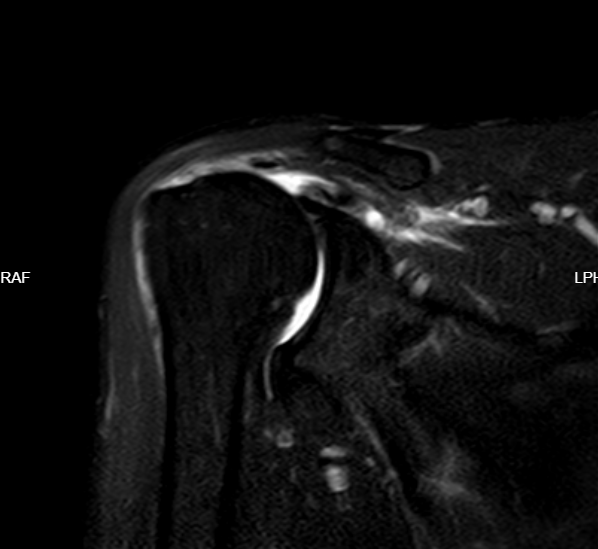

骨科医生经过查体考虑肩关节肩袖损伤。完善肩关节MRI、磁共振等检查 ,显示肱骨明显上移,提示肩袖损伤,肩袖(冈上肌腱)完全断裂。

磁共振显示肩袖(冈上肌腱)完全断裂